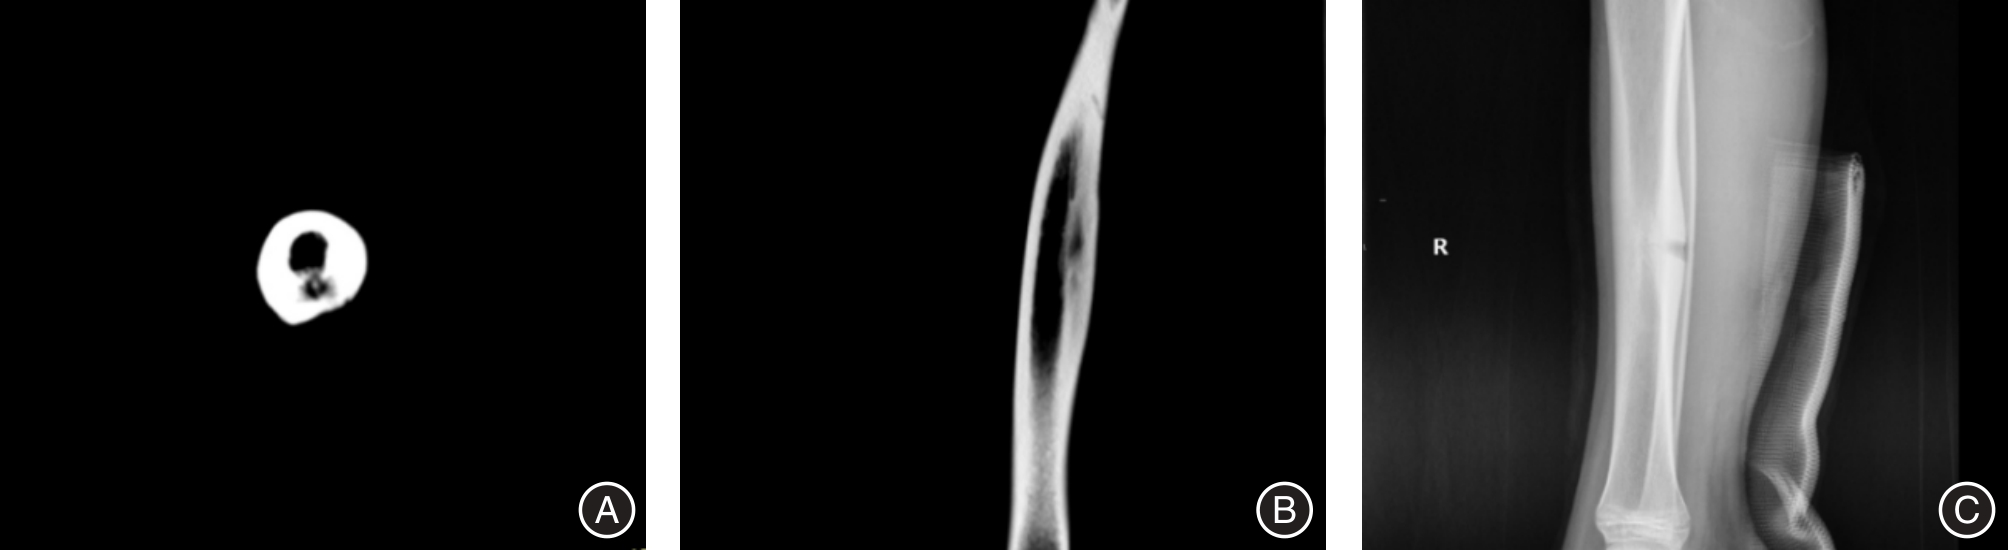

Objective To analyze the clinical efficacy of curettage and sterilization for osteoid osteoma under the guidance of orthopedic surgical robot navigation. Methods A total of 60 patients diagnosed with osteoid osteoma who underwent surgical treatment in the Department of Orthopedics at Foshan Hospital of Traditional Chinese Medicine from January 2018 to June 2025 were recruited. These patients were then divided into an experimental group and a control group, with 30 cases in each group. The control group received traditional curettage and inactivation of the lesion, while the experimental group underwent curettage and inactivation of the lesion under the guidance of an orthopedic surgical robot navigation. A comparison was made between the two groups in terms of the positive detection rate of postoperative pathology, the incidence of complications and postoperative recurrence, the patient satisfaction rate, the VAS pain score, the area of the surgical bone window, the number of bone grafts and internal fixations, the intraoperative blood loss, the operation time (defined as the time from skin incision to the final closure of the operation), the postoperative hospital stay, and the efficacy evaluation. Results The positive detection rate of postoperative pathology in the experimental group was significantly higher than that in the control group (P < 0.05). After the operation, the VAS pain score of the experimental group was significantly lower than that of the control group (P < 0.05). The bone window area, intraoperative blood loss, operation time, and postoperative hospital stay in the experimental group were all significantly lower than those in the control group (P < 0.05). The number of bone grafts in the experimental group was significantly lower than that in the control group (P < 0.05). The bone graft and internal fixation in the experimental group were slightly lower than those in the control group, the satisfaction rate of the experimental group was slightly higher than that of the control group, the total excellent - and - good rate of the experimental group was slightly higher than that of the control group, and the incidence of complications and postoperative recurrence rate of the experimental group were lower than those of the control group, but there was no significant difference (P > 0.05). Conclusions The treatment of osteoid osteoma through curettage and degranulation guided by orthopedic surgical robot navigation can alleviate postoperative pain, reduce surgical trauma, shorten the hospital stay, and offers advantages in terms of pathological positive detection, complications, and postoperative recurrence. Therefore, it is worthy of clinical application.